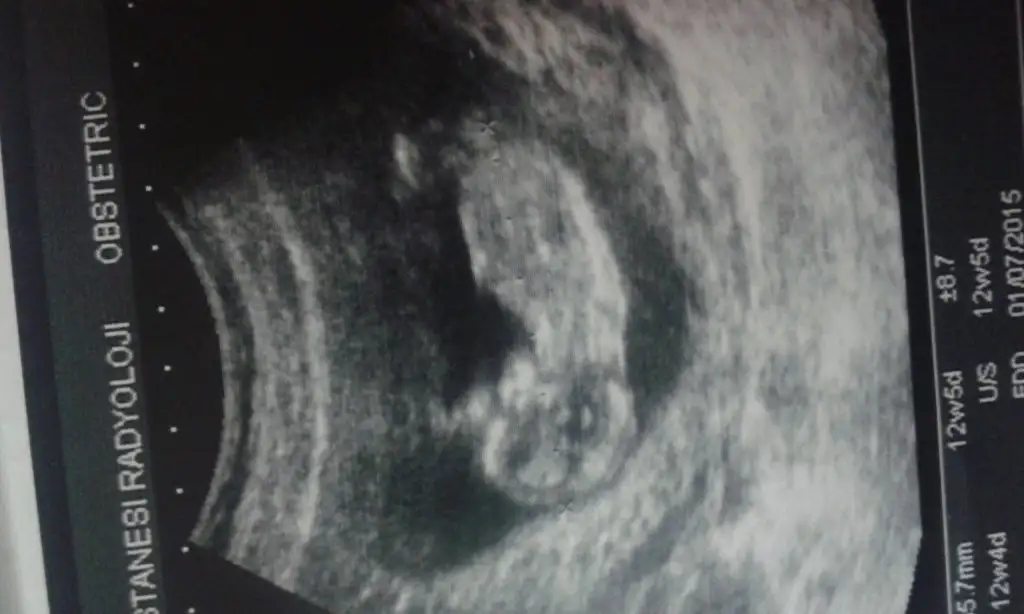

Aaa cok ilgincmiiss ☺☺ pitpit arada hisseder gibi oluyorum ama bebegimmi onu bilmiyorum.hissetmem icin erken degilmi daha ? Bu arada beyaz bebegim ultrasonda.bak goruntuden anlarsan buda resmi ☺☺

Hicbisey asermiyorum canim aksine istahsizim.ikili taramada radyoloji uzmani erkege,dogum doktorum kiza benzetti ☺☺ 13 ocakta randevumuz var bakalim o zamana belli olur sanirim :)